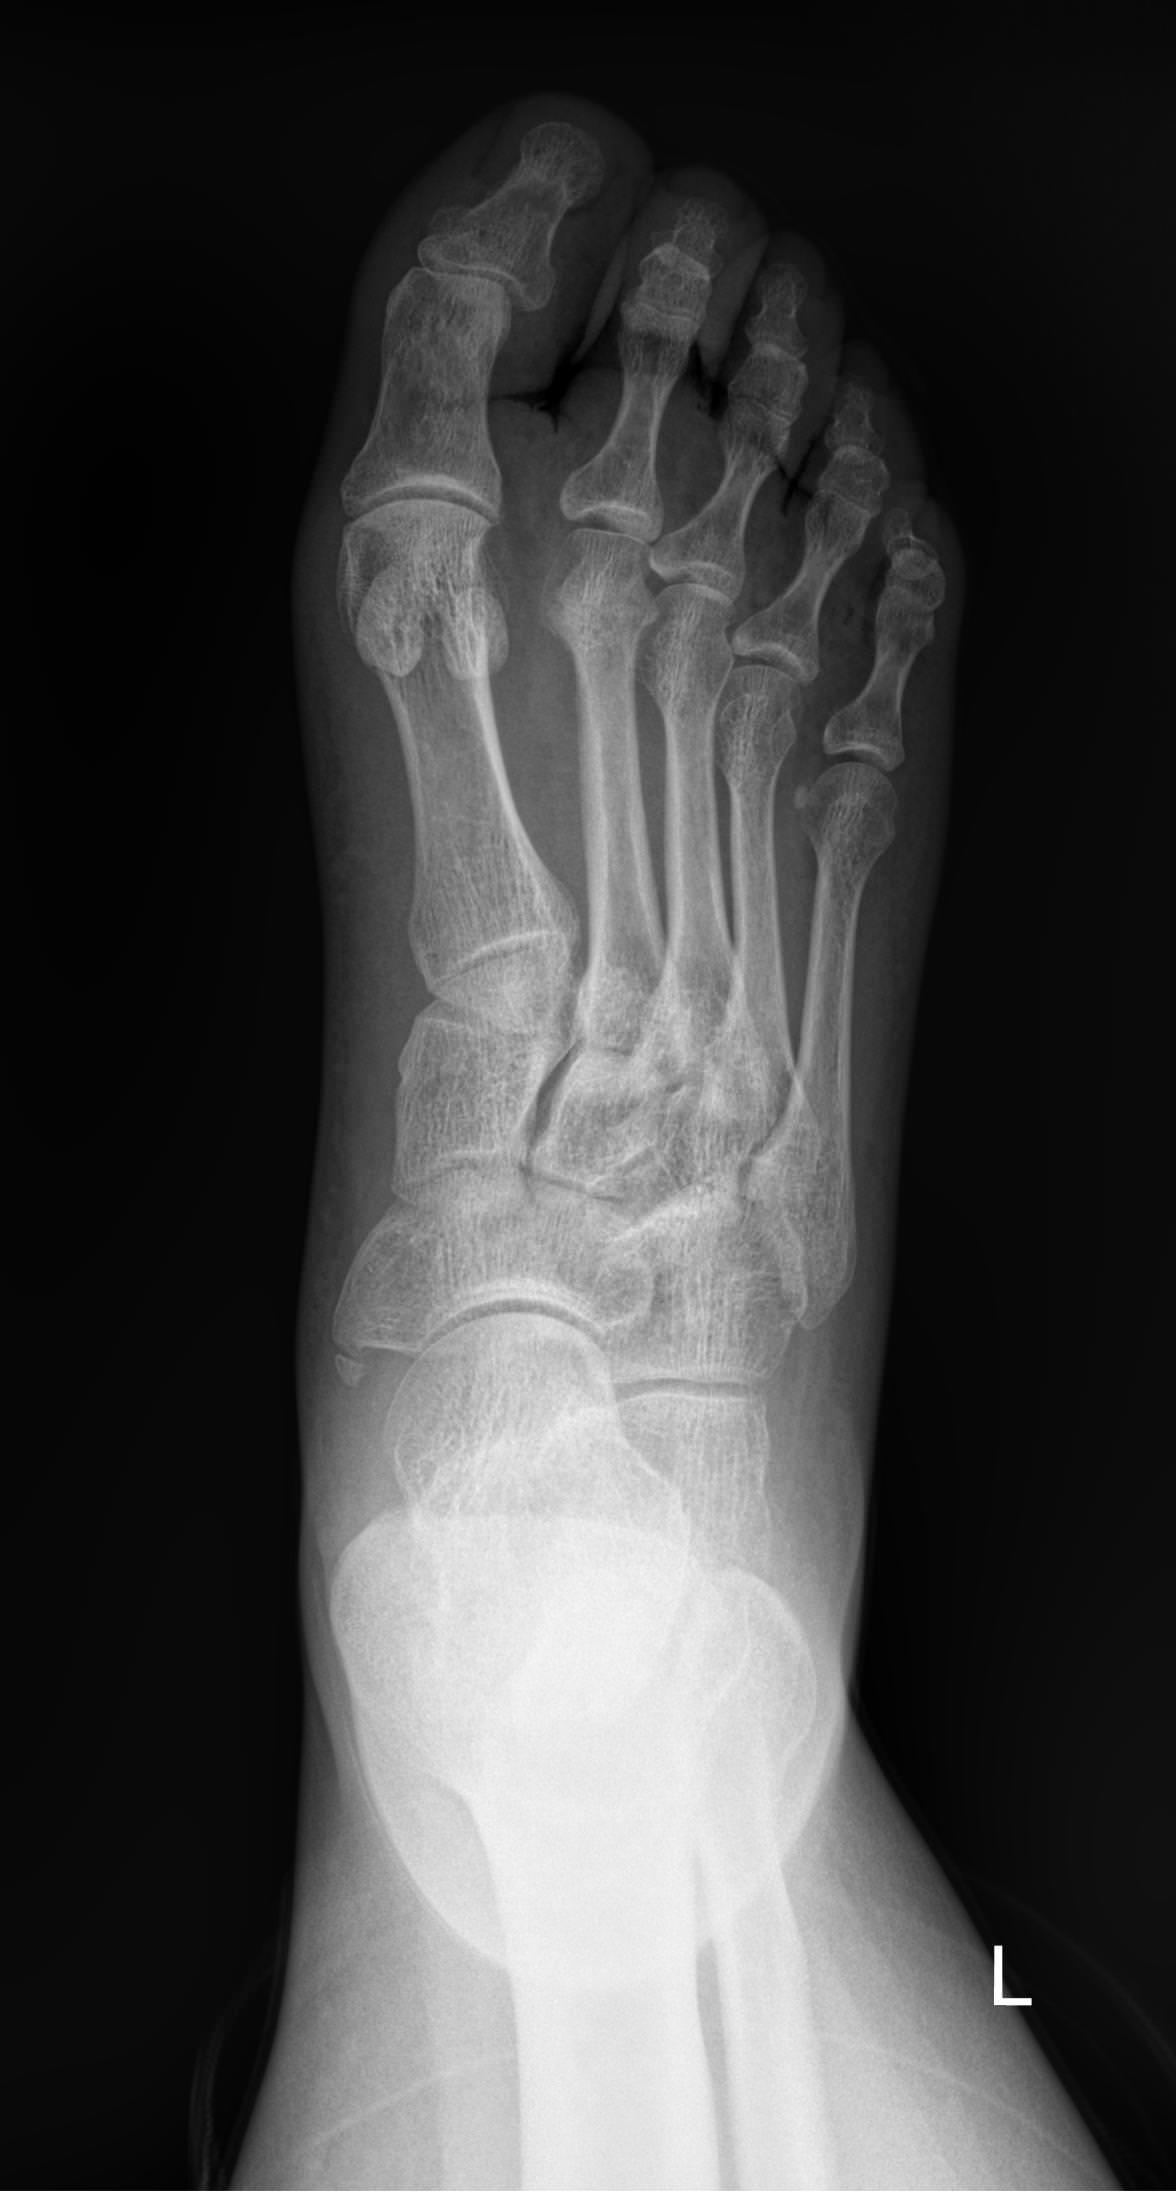

На снимке будут видны:

• Все суставные щели мелких суставов стопы и соответствие суставных поверхностей;

• Изменение в костной ткани и надкостнице;

• Целостность костей и суставов;

• Мягкие ткани стопы и отек в них;

• Новообразования.